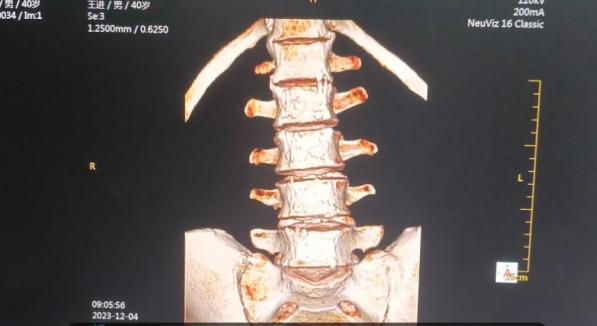

骨破坏三维重建检查发现:腰椎前缘变平直,骨密度增高,形态呈“方椎样”改变,椎间小关节边缘模糊、毛躁,关节间隙变窄;前后纵韧带、棘间韧带增厚、骨化改变。